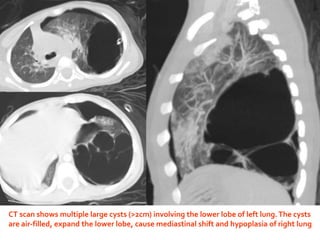

CT scan shows multiple large cysts (>2cm) involving the lower lobe of left lung.The cysts

are air-filled, expand the lower lobe, cause mediastinal shift and hypoplasia of right lung